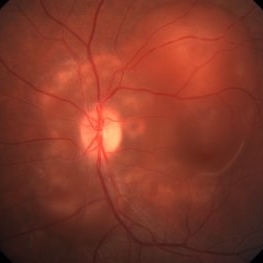

Preeclampsia in a 30-Year-Old - Color Fundus Photograph - RE

Nov 25 2015 by Roy Schwartz, MD

A 30-year-old presented with central scotoma and blurred vision a day following C-section for preeclampsia.

Photographer: Galit Yair Pur

Condition/keywords: preeclampsia